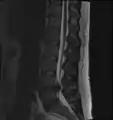

The majority of spinal disc herniations occur in the lumbar spine (95% at L4–L5 or L5–S1).[21] The second most common site is the cervical region (C5–C6, C6–C7). The thoracic region accounts for only 1–2% of cases. Herniations usually occur postero-laterally, at the points where the annulus fibrosus is relatively thin and is not reinforced by the posterior or anterior longitudinal ligament.[21] In the cervical spine, a symptomatic postero-lateral herniation between two vertebrae will impinge on the nerve which exits the spinal canal between those two vertebrae on that side.[21] So, for example, a right postero-lateral herniation of the disc between vertebrae C5 and C6 will impinge on the right C6 spinal nerve. The rest of the spinal cord, however, is oriented differently, so a symptomatic postero-lateral herniation between two vertebrae will impinge on the nerve exiting at the next intervertebral level down.[21]

Herniated lumbar disc

Lumbar disc herniations occur in the back, most often between the fourth and fifth lumbar vertebral bodies or between the fifth and the sacrum. Here, symptoms can be felt in the lower back, buttocks, thigh, anal/genital region (via the perineal nerve), and may radiate into the foot and/or toe. The sciatic nerve is the most commonly affected nerve, causing symptoms of sciatica. The femoral nerve can also be affected and cause the patient to experience a numb, tingling feeling throughout one or both legs and even feet or a burning feeling in the hips and legs.[22] A herniation in the lumbar region often compresses the nerve root exiting at the level below the disc. Thus, a herniation of the L4–5 disc compresses the L5 nerve root, only if the herniation is posterolateral.

• Magnetic resonance imaging is the gold standard study for confirming a suspected LDH. With a diagnostic accuracy of 97%, it is the most sensitive study to visualize a herniated disc due to its significant ability in soft tissue visualization. MRI also has higher inter-observer reliability than other imaging modalities. It suggests disc herniation when it shows an increased T2-weighted signal at the posterior 10% of the disc. Degenerative disc diseases have shown a correlation with Modic type 1 changes. When evaluating for postoperative lumbar radiculopathies, the recommendation is that the MRI is performed with contrast unless otherwise contraindicated. MRI is more effective than CT in distinguishing inflammatory, malignant, or inflammatory etiologies of LDH. It is indicated relatively early in the course of evaluation (<8 weeks) when the patient presents with relative indications like significant pain, neurological motor deficits, and cauda equina syndrome. Diffusion tensor imaging is a type of MRI sequence used for detecting microstructural changes in the nerve root. It may be beneficial in understanding the changes that occur after herniated lumbar disc compresses a nerve root, and might help in differentiating the patients that need surgical intervention. In patients with a high suspicion of radiculopathy due to lumbar disc herniation, yet the MRI is equivocal or negative, nerve conduction studies are indicated.[44] T2-weighted images allow for clear visualization of protruded disc material in the spinal canal.